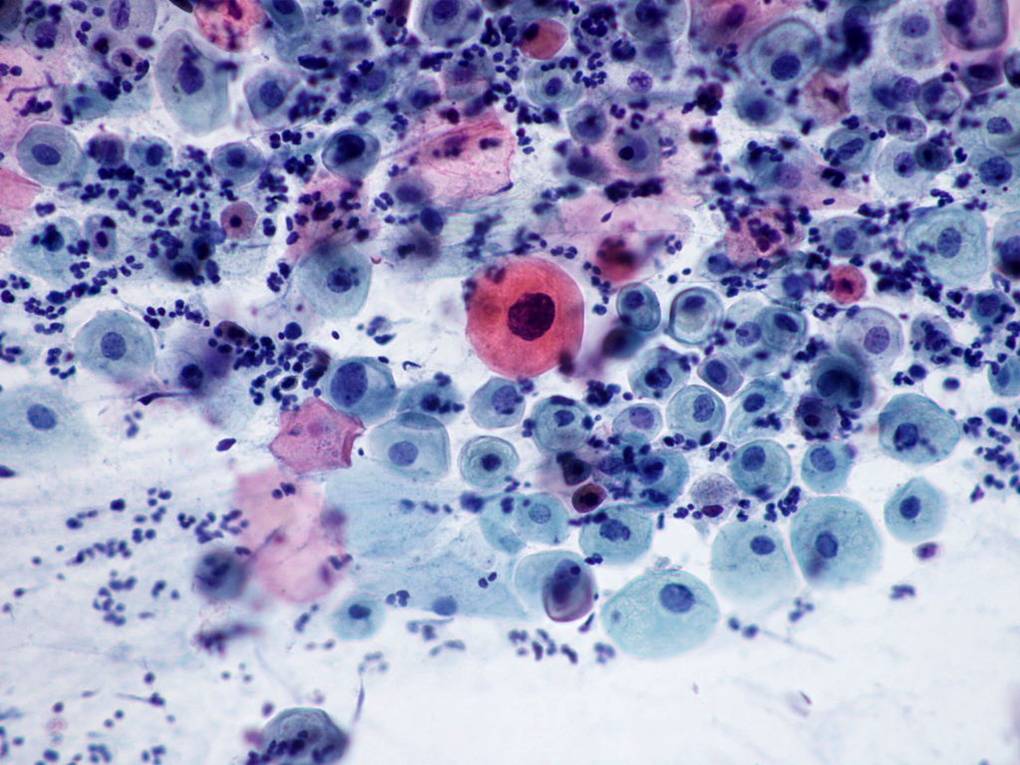

TBS-17修复细胞

TBS-18修复细胞